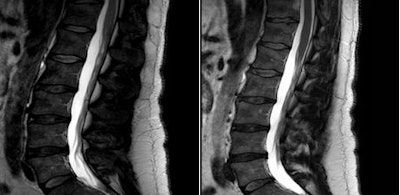

![]() |

| The lumbar spine shows reduced shading and improved image quality when comparing standard MRI (left) and multitransmit MRI (right) with T2-weighted imaging. |